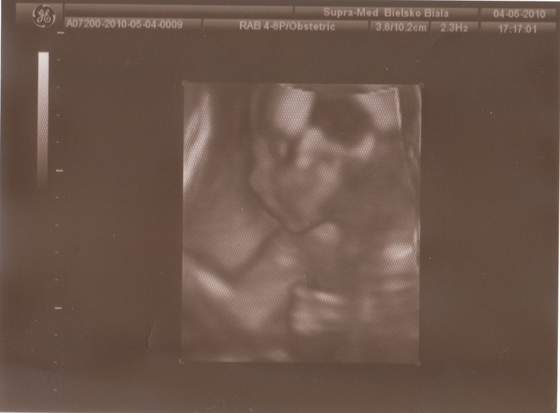

a to w 10 tygodniu ( troche niewyrazne )

no i 14/15 tydzien - pierwesze zdjecie to dwie glowki razem , a nastepne to kazdy dzidziul z osobna))))